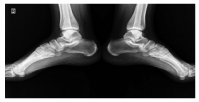

Dose reduction was used in patients with moderate and severe back pain, constituting 37.2% of the patients describing the complaint. The vast majority of these patients responded to dose reduction, while eight (10.2%) patients needed to use non-steroidal anti-inflammatory drugs for pain relief. Sacroiliitis was present in four (4%) patients, including three females and one male. There was no statistically significant difference between the sexes for sacroiliitis development (p=0.25). Bilateral sacroiliitis was detected in one patient (Figure 1). Sacroiliitis regressed 1.5 to 2.5 months after isotretinoin treatment cessation in all patients. The patients diagnosed with sacroiliitis were followed for six months. Three (3%) patients described myalgia, which was of mild severity and did not require additional treatment. Among these patients, two female patients also described low back pain. Creatine kinase (CK) elevation was observed in 18 (18.1%) patients, including 13 males and two females, one to three months after the beginning of treatment (p=0.1). The elevated CK values ranged between 233 and 940 IU and returned to normal levels after dose reduction. One (1%) female patients who was on low-dose isotretinoin treatment (0.5 mg/kg) was diagnosed with enthesitis at three months of treatment (Figure 2).

Enthesopathy is a reported side effect of isotretinoin and usually develops after long-term isotretinoin use.[37,38] However, cases associated with short-term isotretinoin treatment have also been reported in the literature. Tendinitis of the Achilles tendon is a known side effect of isotretinoin and has been reported in 9.5% of patients.4 A close relationship between Achilles tendinitis and isotretinoin dose has also been described.[39,40] In our study, the patient who developed tendinitis was on low-dose isotretinoin treatment. Dose reduction and interruption can be considered in patients developing tendinitis.[39] The symptoms of the patient in the current study regressed with the cessation of treatment.